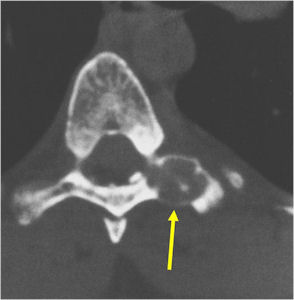

- Spine (40% of cases; usually posterior elements)

CT Scan:

- More useful for detecting mineralization and evaluating extent of bone destruction than plain X-ray

- The periosteum remains intact around the soft tissue component. Might need a CT scan to detect the subtle calcification (Egg Shell Rim of Calcification) associated with an intact periosteal reaction

- The lesion may be entirely radiolucent but usually shows some degree of mineralization. Mineralization may appear stippled like cartilage but do not see chondroid pathologically. Mineralization is sometimes better detected on a CT scan rather than an x-ray.